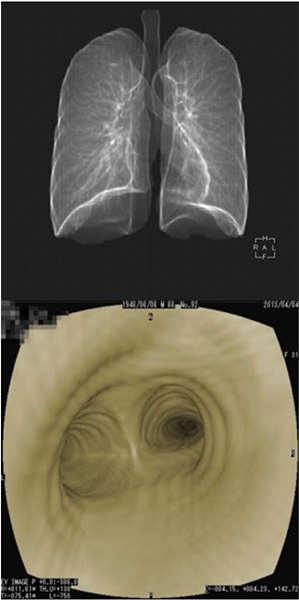

当院では、仮想気管支内視鏡検査は肺と気管支が一度に評価可能です。

仮想気管支内視鏡

CTによる仮想気管支内視鏡検査肺と気管支の評価が一度に可能です。